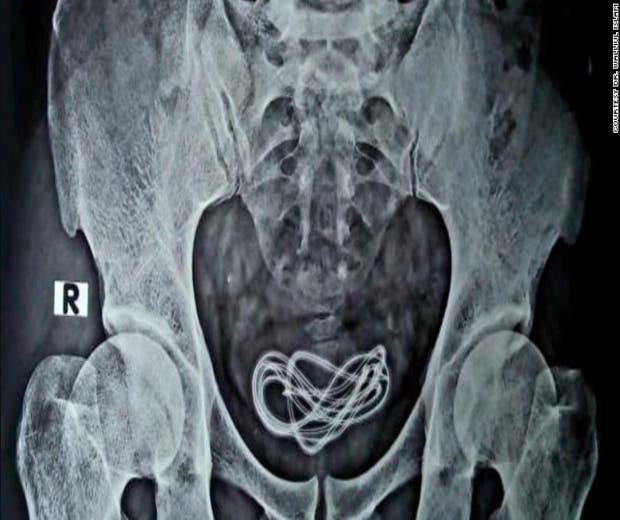

Após um raio-x, os médicos identificaram que o homem tinha um cabo carregador de 60 centímetros de comprimento dentro da bexiga, que foi inserido através da uretra, o tubo que vai do pênis à bexiga. “Então eu fiz uma incisão lá e puxei o cabo, que na verdade era um cabo de carregador com mais de 60 centímetros de comprimento”, disse Islam.